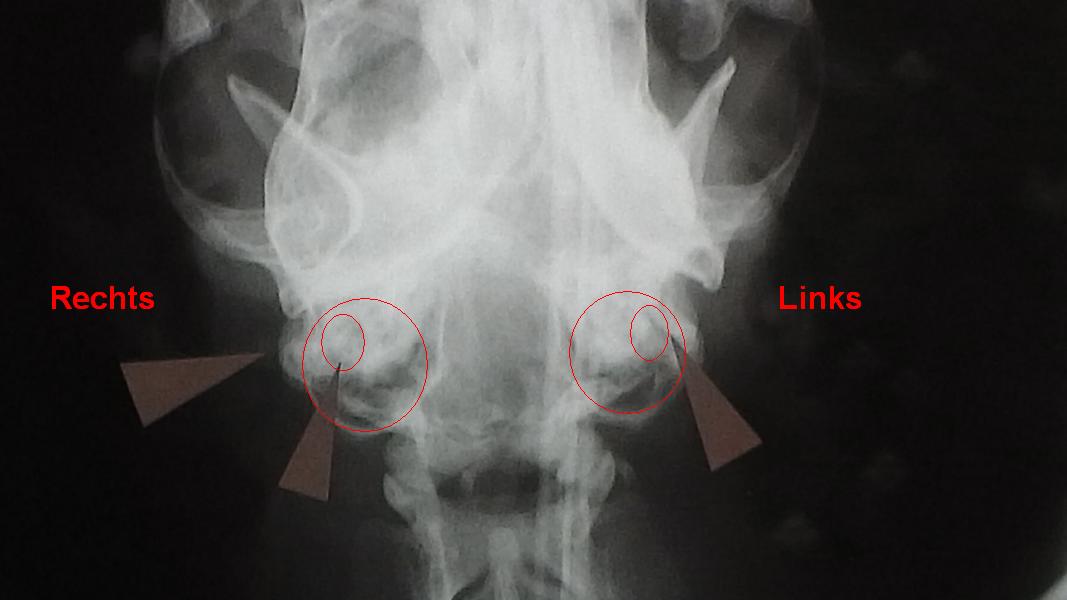

Rechts ist die gesunde Seite. Die linke Seite stellt sich durch den Polypen links anders dar. Entzündliche Ohrpolypen des knöchernen Gehörganges können durch Röntgen-aufnahmen dargestellt werden. Zur besseren Orientierung sind die Areale im neben-stehenden Bild rot umkreist.

Rechts zeichnet sich der Gehörgang (Pfeile), Paukenhöhle (großer Kreis) und kleine dorsale Kammer der Paukenhöhle (kleine rot umrandete Region) dunkler und konturiert ab. Der Polyp ist kontrastreicher. Der Bezirk ist heller.Deshalb kann die kleine Kammer nicht vom umliegenden knöchernen Bereich unterschieden werden.

Der Verdacht auf einen im Gehörgang sitzenden Polypen ist durch eine einfache Ohruntersuchung überprüfbar. Im Anschluss empfehlen wir an erster Stelle die vollständige Untersuchung der Ohren und des Rachens unter Sedation/Narkose im Verbund mit Röntgenaufnahmen des Schädels und des Brustkorbes. An Laboruntersuchungen empfehlen vor ab einen komplettes Blutprofil, Ausschluss von FIV (Felines Immunschwäche Virus = Katzenaids); FIP (Feline Infektiöse Peritonitis); FeLV (Felines Leukosevirus) sowie eine Urinanalyse. Das nebenstehende Röntgenbild eines Patienten mit Polypen im linken Ohr zeigt erhebliche Zunahme der Aufhellung und Füllung (Polyp) der knöchernen Bestandteile des linken Ohres. Dies wird insbesondere im Vergleich mit der rechten, nicht betroffenen Seite deutlich. Die Pfeile markieren die Paukenhöhle der Katze. Als Besonderheit ist die Paukenhöhle der Katze durch eine Wand (Septum) zweigekammert. Beide Kammern müssen bei einer Ventralen Bulla Osteotomie eröffnet werden.